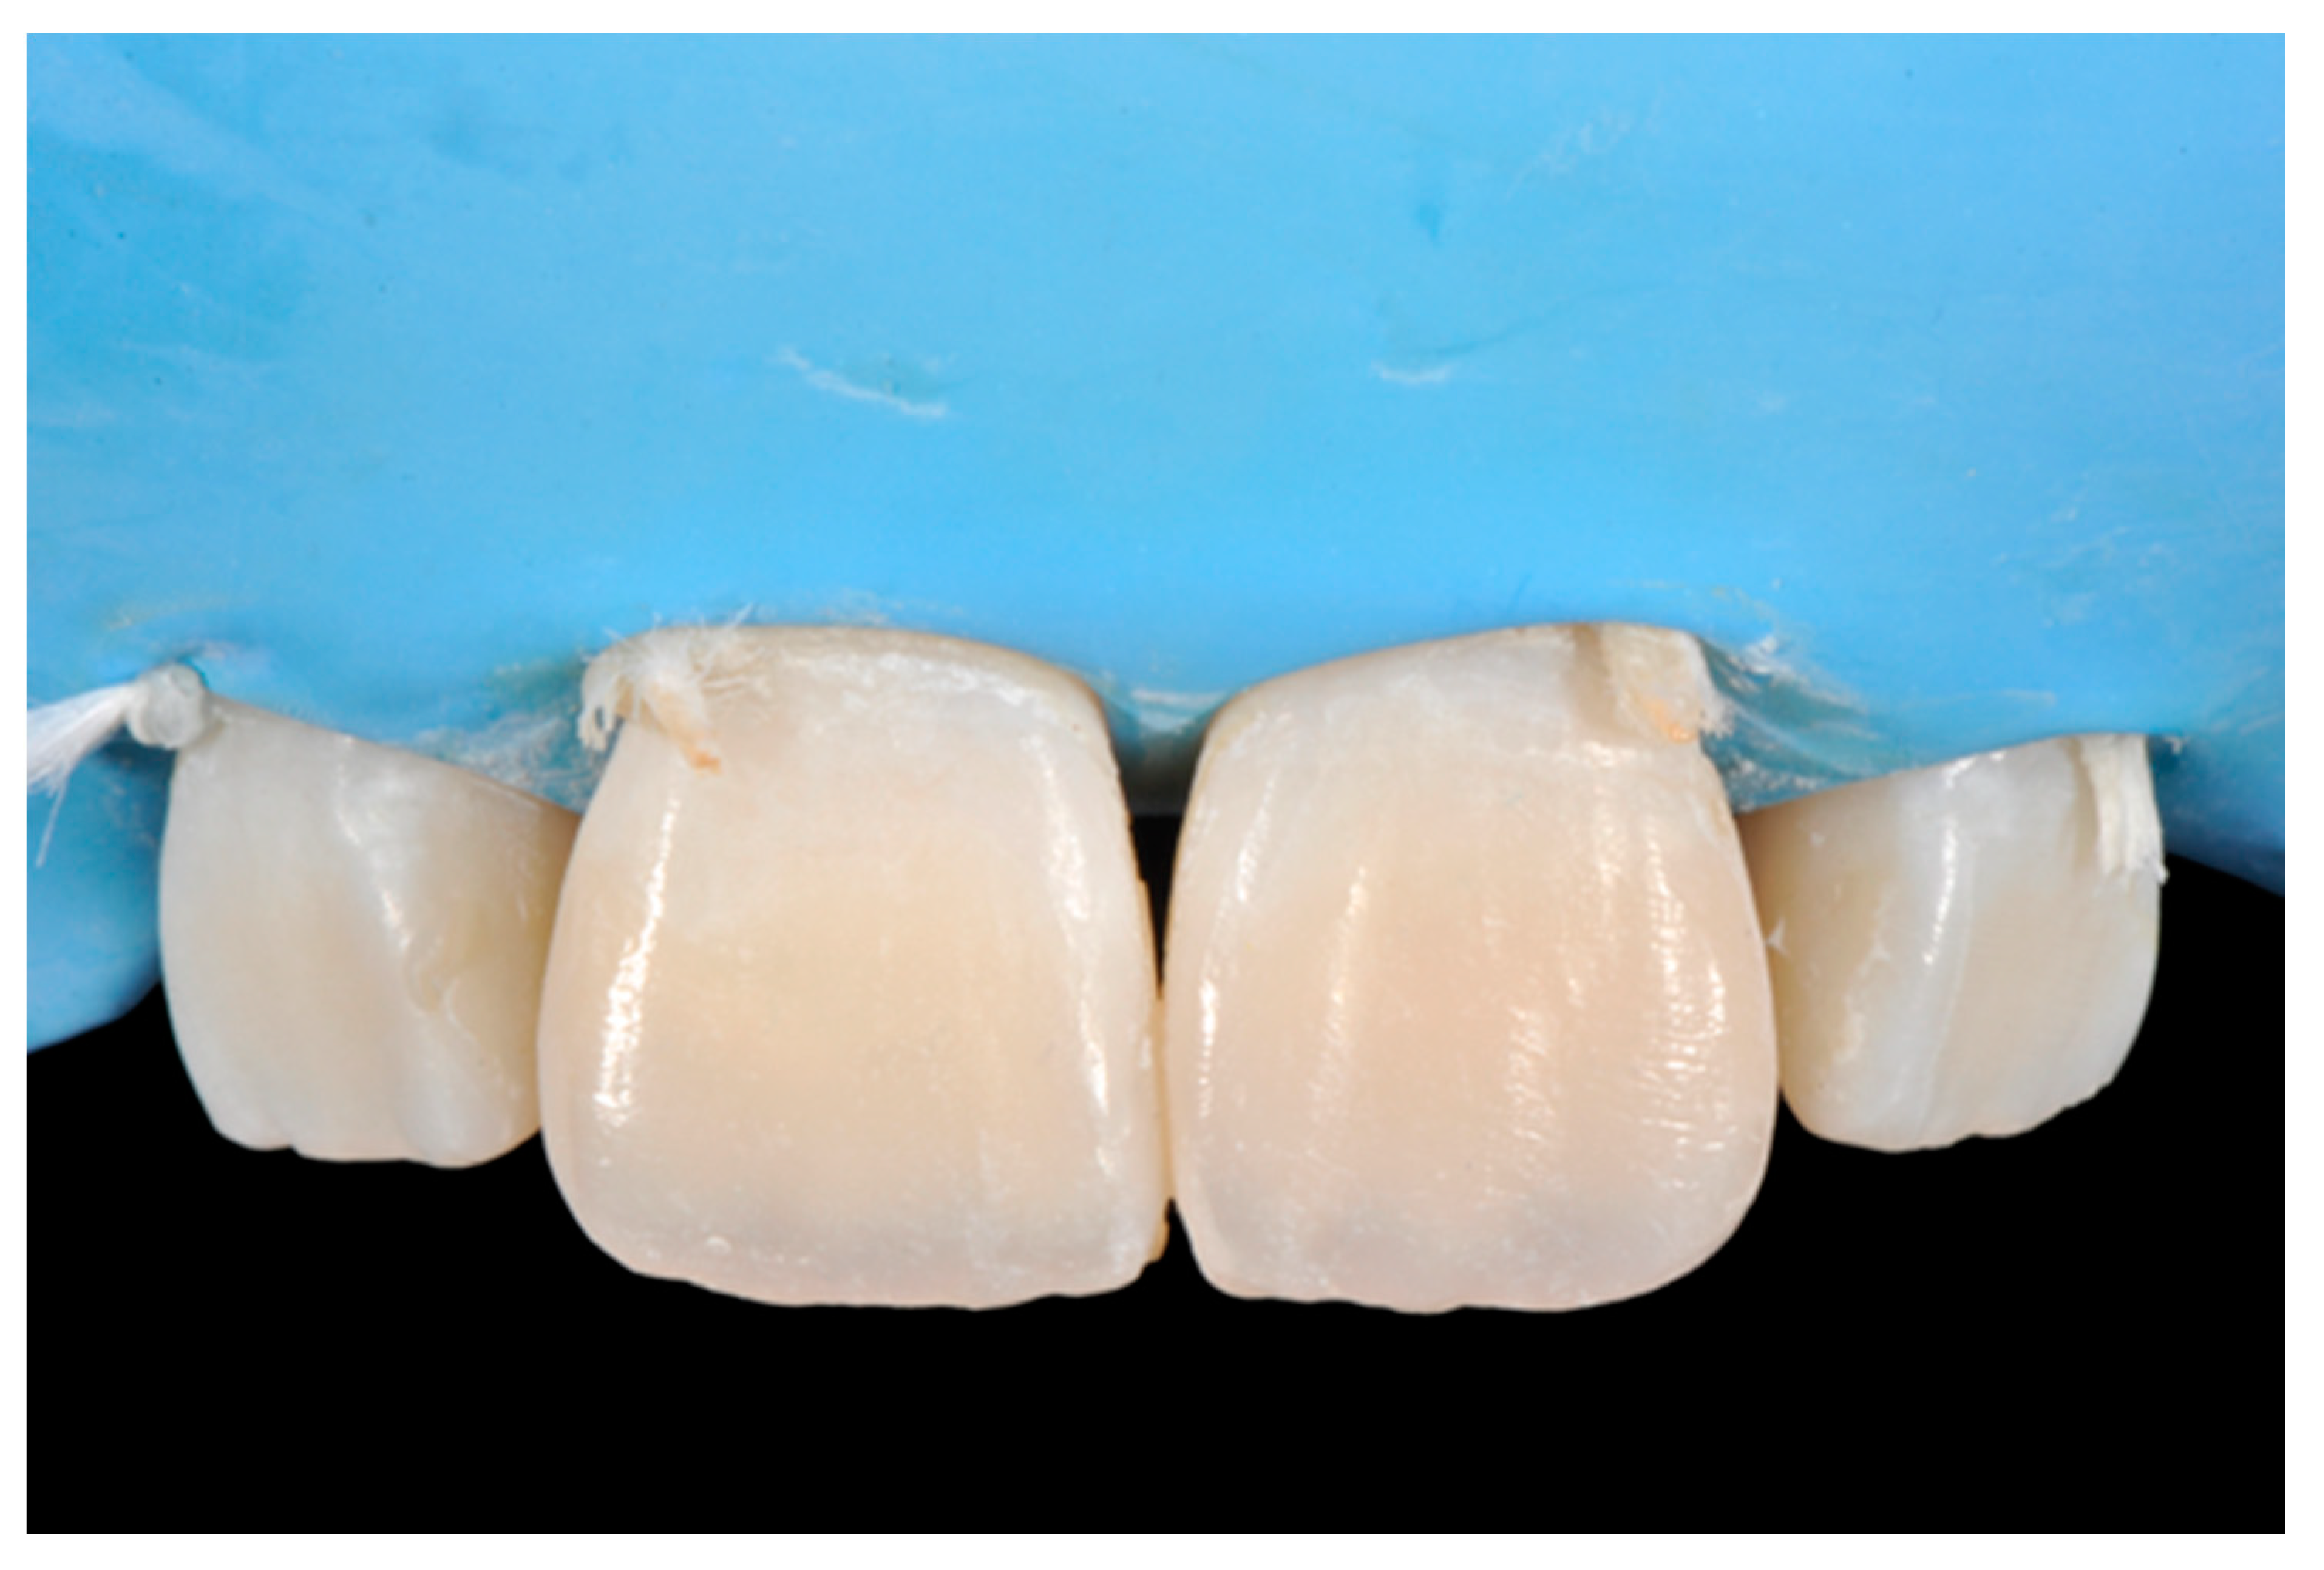

Finishing and polishing procedures were performed with a diamond bur (WL 268 014 Horico, Berlin, Germany), silicone points (Identoflex, Kerr, Bioggio, Switzerland) brushes (Jiffy Goat Air Brushes, Ultradent Products, South Jordan, UT, USA), and diamond pastes (Diamond Polish Mint, Ultradent Products, South Jordan, UT, USA) (Figure 13 and Figure 14). Satisfactory clinical and radiographic outcome was considered satisfactory at 3-months, 1-year, and 5-years post-operative (Figure 15, Figure 16, Figure 17, Figure 18 and Figure 19).

Figure 15.

Three months post-operative. Reprinted from Restauri diretti nei settori anteriori, G. Paolone, S. Scolavino, © 2021, with permission from Quintessence Publishing Italy.

Figure 16.

One year post-operative. Reprinted from Restauri diretti nei settori anteriori, G. Paolone, S. Scolavino, © 2021, with permission from Quintessence Publishing Italy.